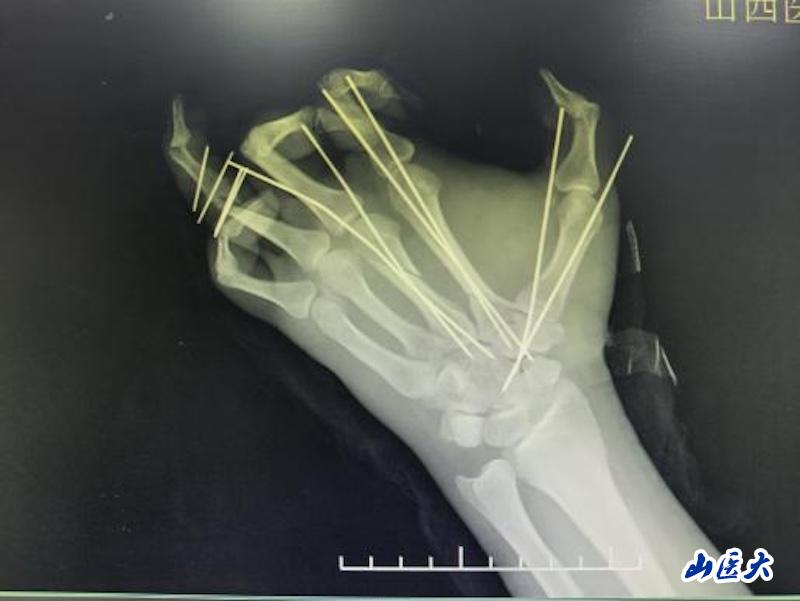

手掌血管直径仅0.3-0.5毫米,不足普通针孔大小;医生需要在手术显微镜下,使用比头发丝更细的11-0缝线,将断裂的血管重新吻合。手掌包含27块骨骼、多条肌腱、复杂的神经血管网络;再植手术必须依次完成骨骼固定、伸屈肌腱修复、神经对接、动脉静脉吻合等多个环节,每个环节都要求极高的精度和恰当的顺序安排。

无影灯下,李广荣、武永辉、房格等医师全神贯注。首先彻底清创,标记重要的神经和血管;接着固定掌骨,建立稳定的骨架;然后开始最关键的环节——血管吻合。然后是神经吻合,这关系到手掌未来的感觉和功能恢复。最后是肌腱缝合,为手部运动功能打下基础。6个小时,在高度集中和精细操作中转瞬即逝。当最后一针缝合完成,小张离断的手掌重新回到了他的腕部,血运良好。